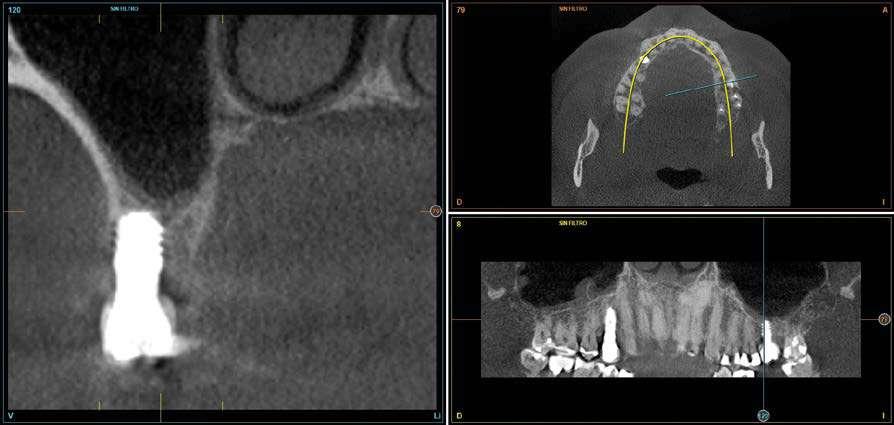

Figuras 3 y 4 . Corte del Cone-beam dental tras la exodoncia y regeneración del alveolo con Endoret-PRGF cuatro semanas después. Podemos observar la atrofia ósea en sentido vertical de la zona con una altura máxima de 3 mm. La planificación como podemos visualizar será para la realización de una elevación transcrestal mínima y la colocación de un implante extracorto.

Figura 12. Mantenimiento de la altura ósea lograda y de la estabilidad del implante al año de carga visualizada en cone-beam.

Figura 13. Estabilidad del tratamiento a los 7 años. No existe pérdida ósea asociada ni problemas relacionados con la prótesis.